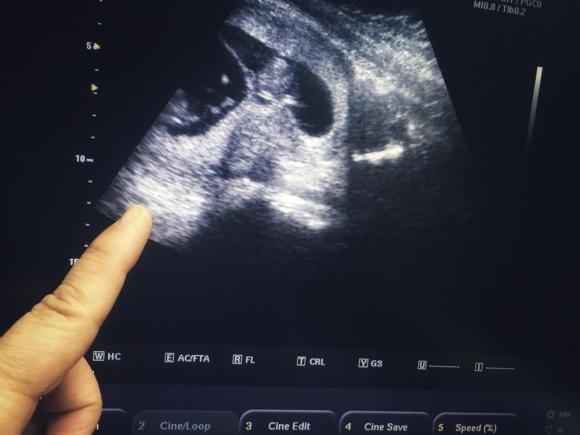

Descoperirea a fost făcută la o ecografie, în timp ce mama copiilor, în vârstă de 28 de ani. era însărcinată. Dacă prima ecografie de rutină sugera că gemenii sunt identici, împărțind placenta în uter, la a doua ecografie medicii au descoperit că bebelușii erau un băiețel și o fetiță.

„Când mama a revenit la control pentru o ecografie, la câteva luni după prima ecografie, am văzut că unul dintre gemeni era băiat, celălalt era fetiță. În acel moment am început să studiem particularitățile genetice ale celor doi”, spune el.